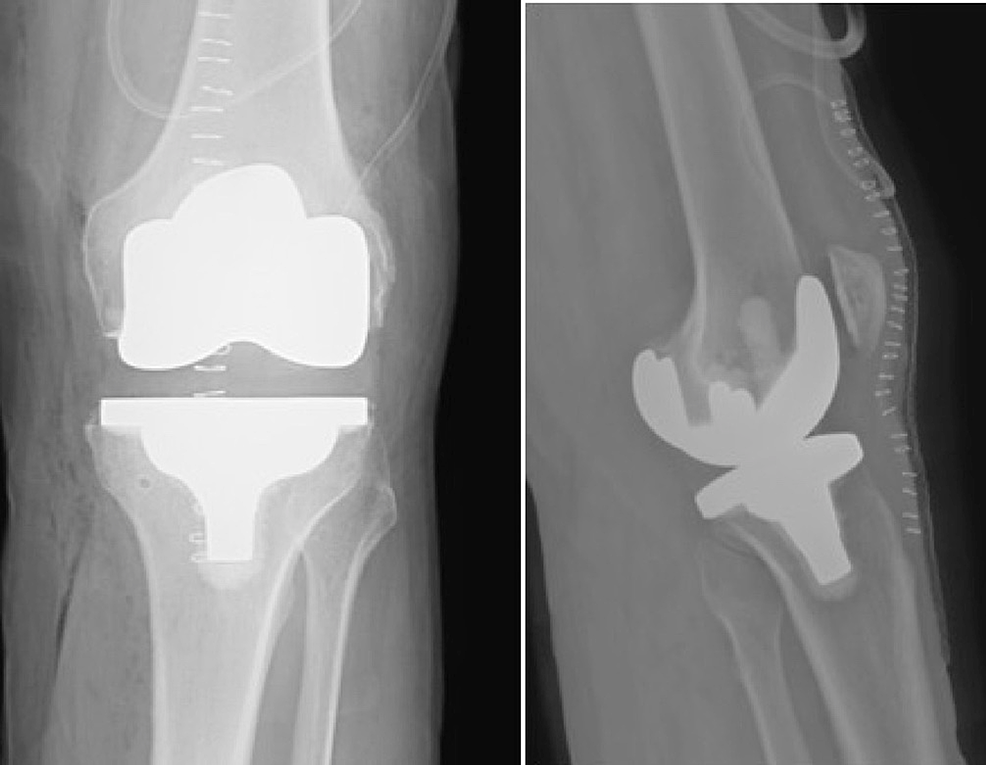

total knee replacement xray